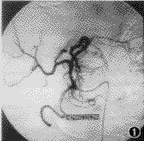

1.临床疗效判定: 栓塞前CT平扫见有低密度区域,增强见典型“早出晚归”现象。DSA显示早动脉期即出现边界锐利的点状血窦,沿瘤体周边分布,随时间推移,瘤体染色自外周向中心扩展,边界变得模糊,血窦染色排空明显延迟。注入PLE后6例CHL肿瘤血窦均明显染色(图1,2)。栓塞后1~6个月CT平扫见瘤体内碘油沉积,肿瘤直径明显缩小(图3,4)。栓塞前肿瘤直径平均为(6.8±1.5) cm,栓塞后平均为(2.5±2.1) cm。栓塞前后肿瘤直径经t检验,有显著性差异(t=4.485,P<0.05)(表1)。

图1 肝动脉造影显示肝左叶肿瘤血窦不均匀染色

图2 平阳霉素碘油乳剂栓塞后沉积于肿瘤血窦中